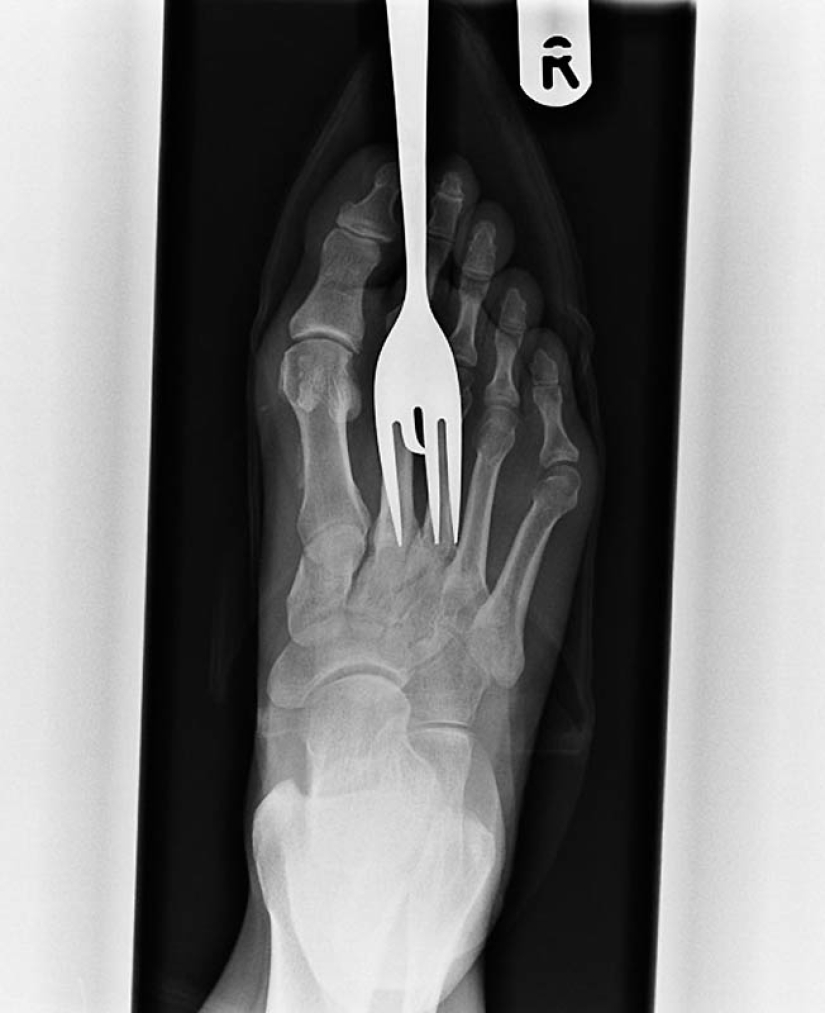

10. Another patient who stepped on a fork.